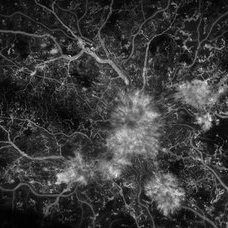

PDR and CRVO after COVID-19

Jan 20 2022 by Kyle D Kovacs, MD

Fluorescein angiogram of 21 year-old male with Type 1 DM, with new diagnosis of PDR and CRVO 6 months following hospitalization for DKA and COVID-19 pneumonia, noted acute deterioration in vision during hospitalization. Bilateral non-perfusion and florid neovascularization.

Imaging device: Optos Silverstone

Condition/keywords: COVID-19, Diabetes mellitus type 1, florid neovascularization, ischemic CRVO, proliferative diabetic retinopathy (PDR)